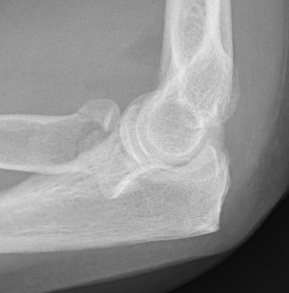

Type 3: Severely comminuted fracture / Non reconstructable

Type 3 radial head fractures